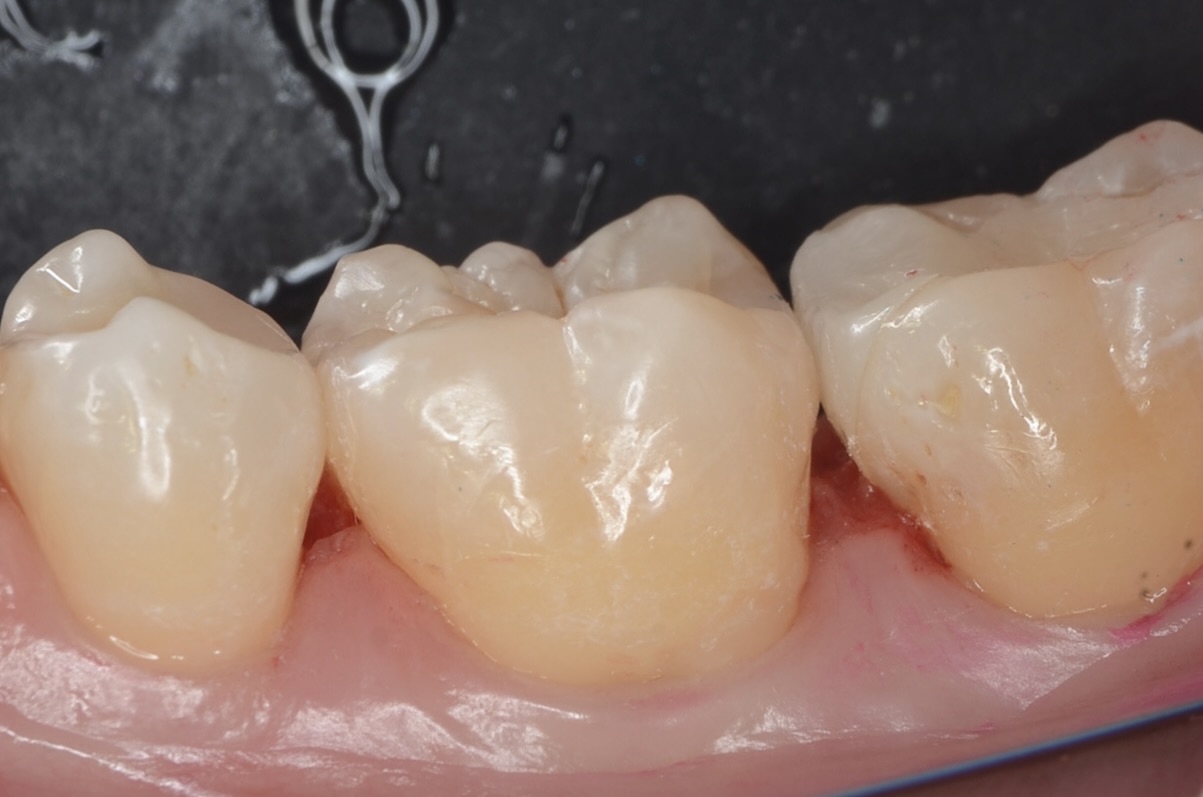

硎磨

自然な見た目に仕上がりました。噛み合わせも問題ありません。本当の審美歯科とは、見た目の美しさ・機能・清掃性が伴って成立します。 -

頬側面観

-